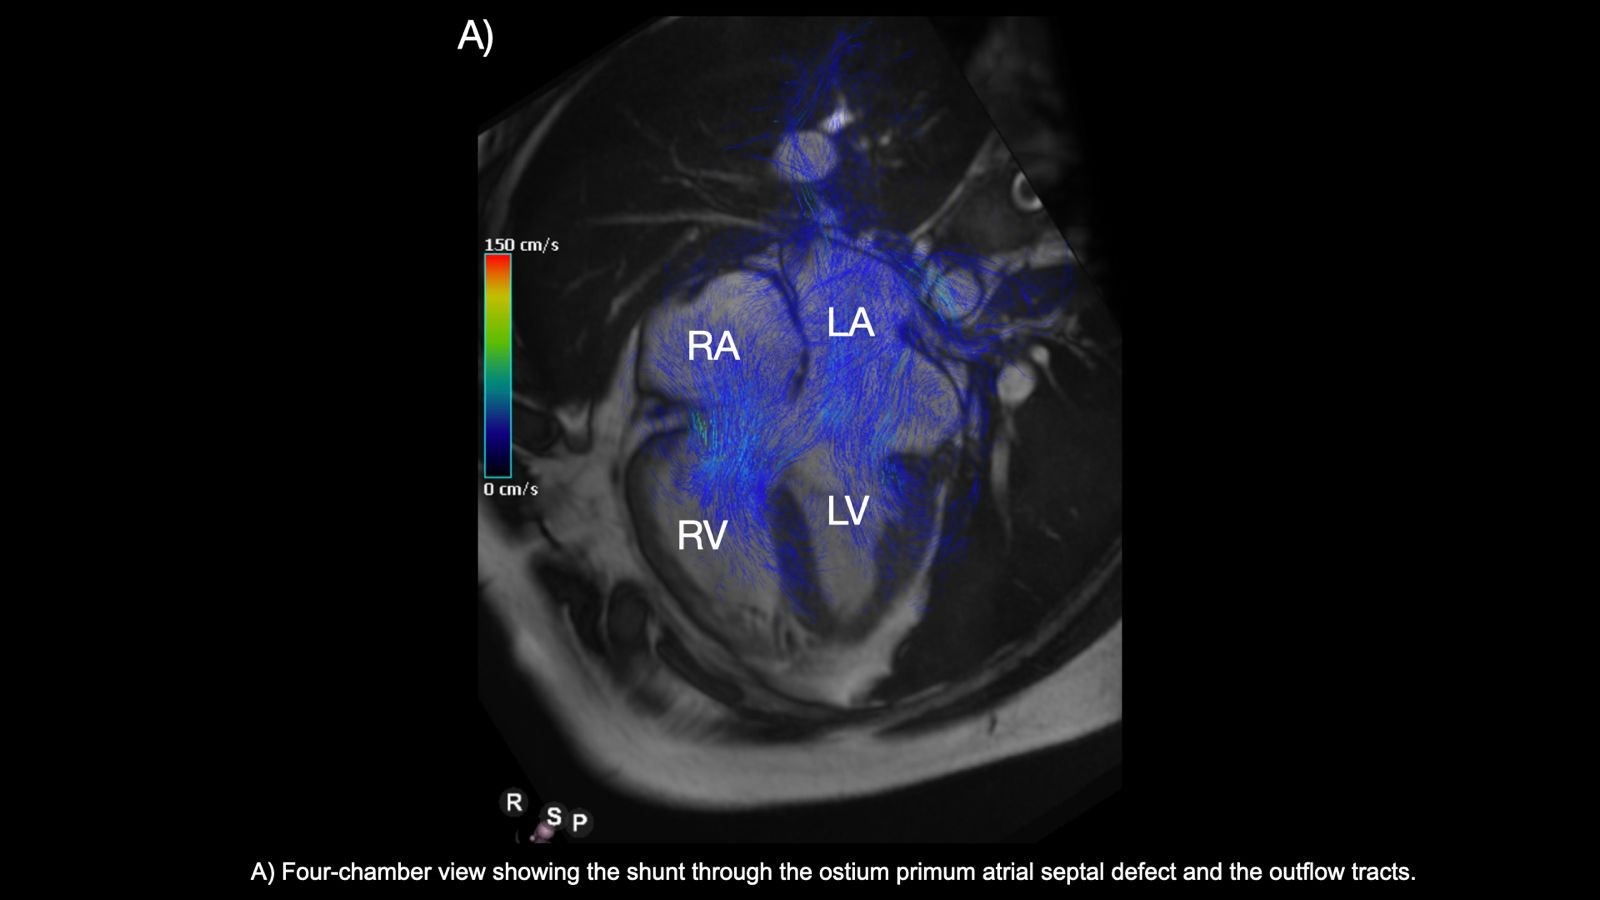

Image B